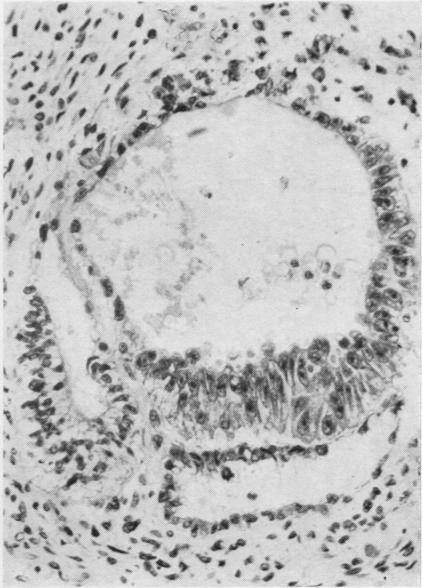

Developmental stages of embryo-like bodies in teratoma testis.